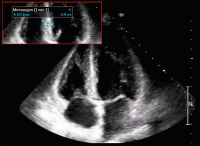

Abbildung 1: Echokardiographie bei Erstvorstellung